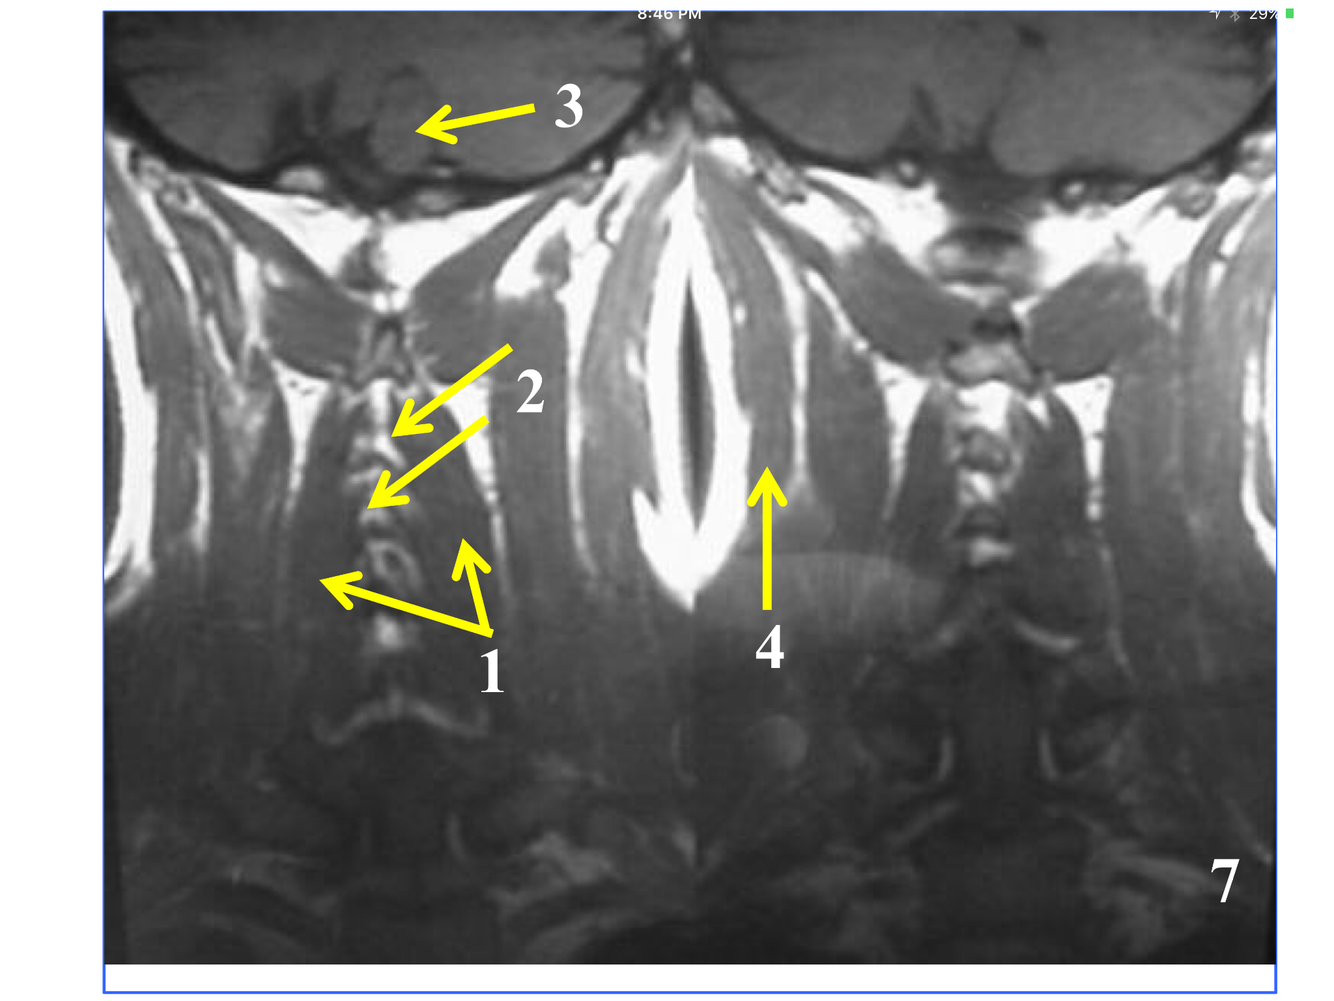

*near the atlantooccipital joint

**the tubercle of the anterior arch is where teh arrow is pointing, but not seen here.

* Just superior to atlantoaxial joint

* The stack of inferior and superior articulating processes, and the zygapophyseal joints they form

*Comprised of the inferior and superior articulating processes, and the zygapophyseal joints they form